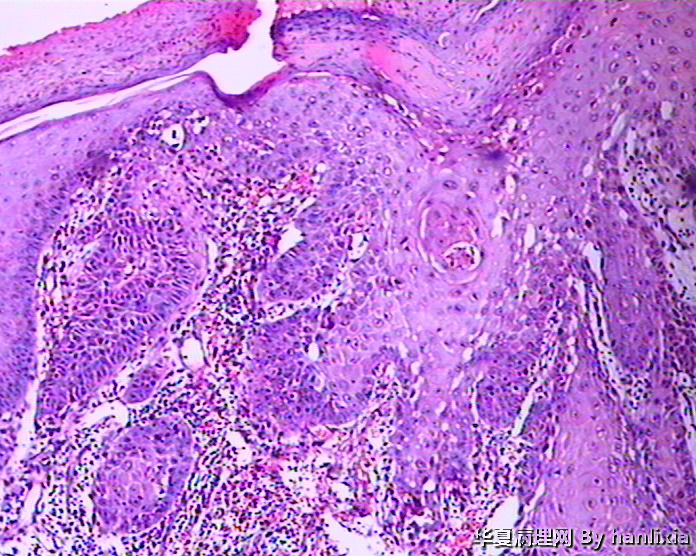

男性患者,50岁,发现面部皮肤(耳旁)肿物一年余,色黑。

高分化鳞状细胞癌

高分化鳞癌可能,也可能AK基础上发展而来的浅表型鳞癌?

部分区域突破基底膜,应该诊断鳞癌,由日光性角化发展过来的!